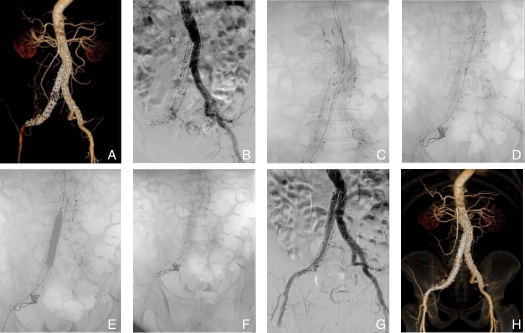

图1 男性患者,EVAR术后6个月出现左侧下肢间歇性跛行,考虑左侧ILO A:术前腹主动脉CTA;B:术中腹主动脉造影;C:导丝导管通过左侧ILO段;D:5.5 F Fogarty取栓,导管通过髂支近端时受压变形,提示髂支近端重度狭窄;E:对髂支内病变段进行球囊扩张;F:髂支近端植入自膨式BMS;G:造影显示左侧髂支恢复正常血流;H:出院时复查主动脉CTA显示腹主动脉双侧髂动脉管腔无明显狭窄Fig.1 A male patient presented with intermittent claudication in the left lower limb 6 months after EVAR, indicating left-sided ILO A: Preoperative abdominal aortic CTA; B: Intraoperative abdominal aortic angiography; C: Guidewire catheter passing through the left-sided ILO segment; D: 5.5 F Fogarty thrombectomy catheter being compressed and deformed when passing through the proximal iliac limb, indicating severe stenosis at the proximal iliac limb; E: Balloon dilation of the diseased segment in the iliac limb; F: Self-expanding BMS implanted in the proximal iliac limb; G: Angiography showing normal blood flow in the left iliac limb; H: Abdominal aortic CTA before discharge showing no significant stenosis in the lumens of both iliac arteries